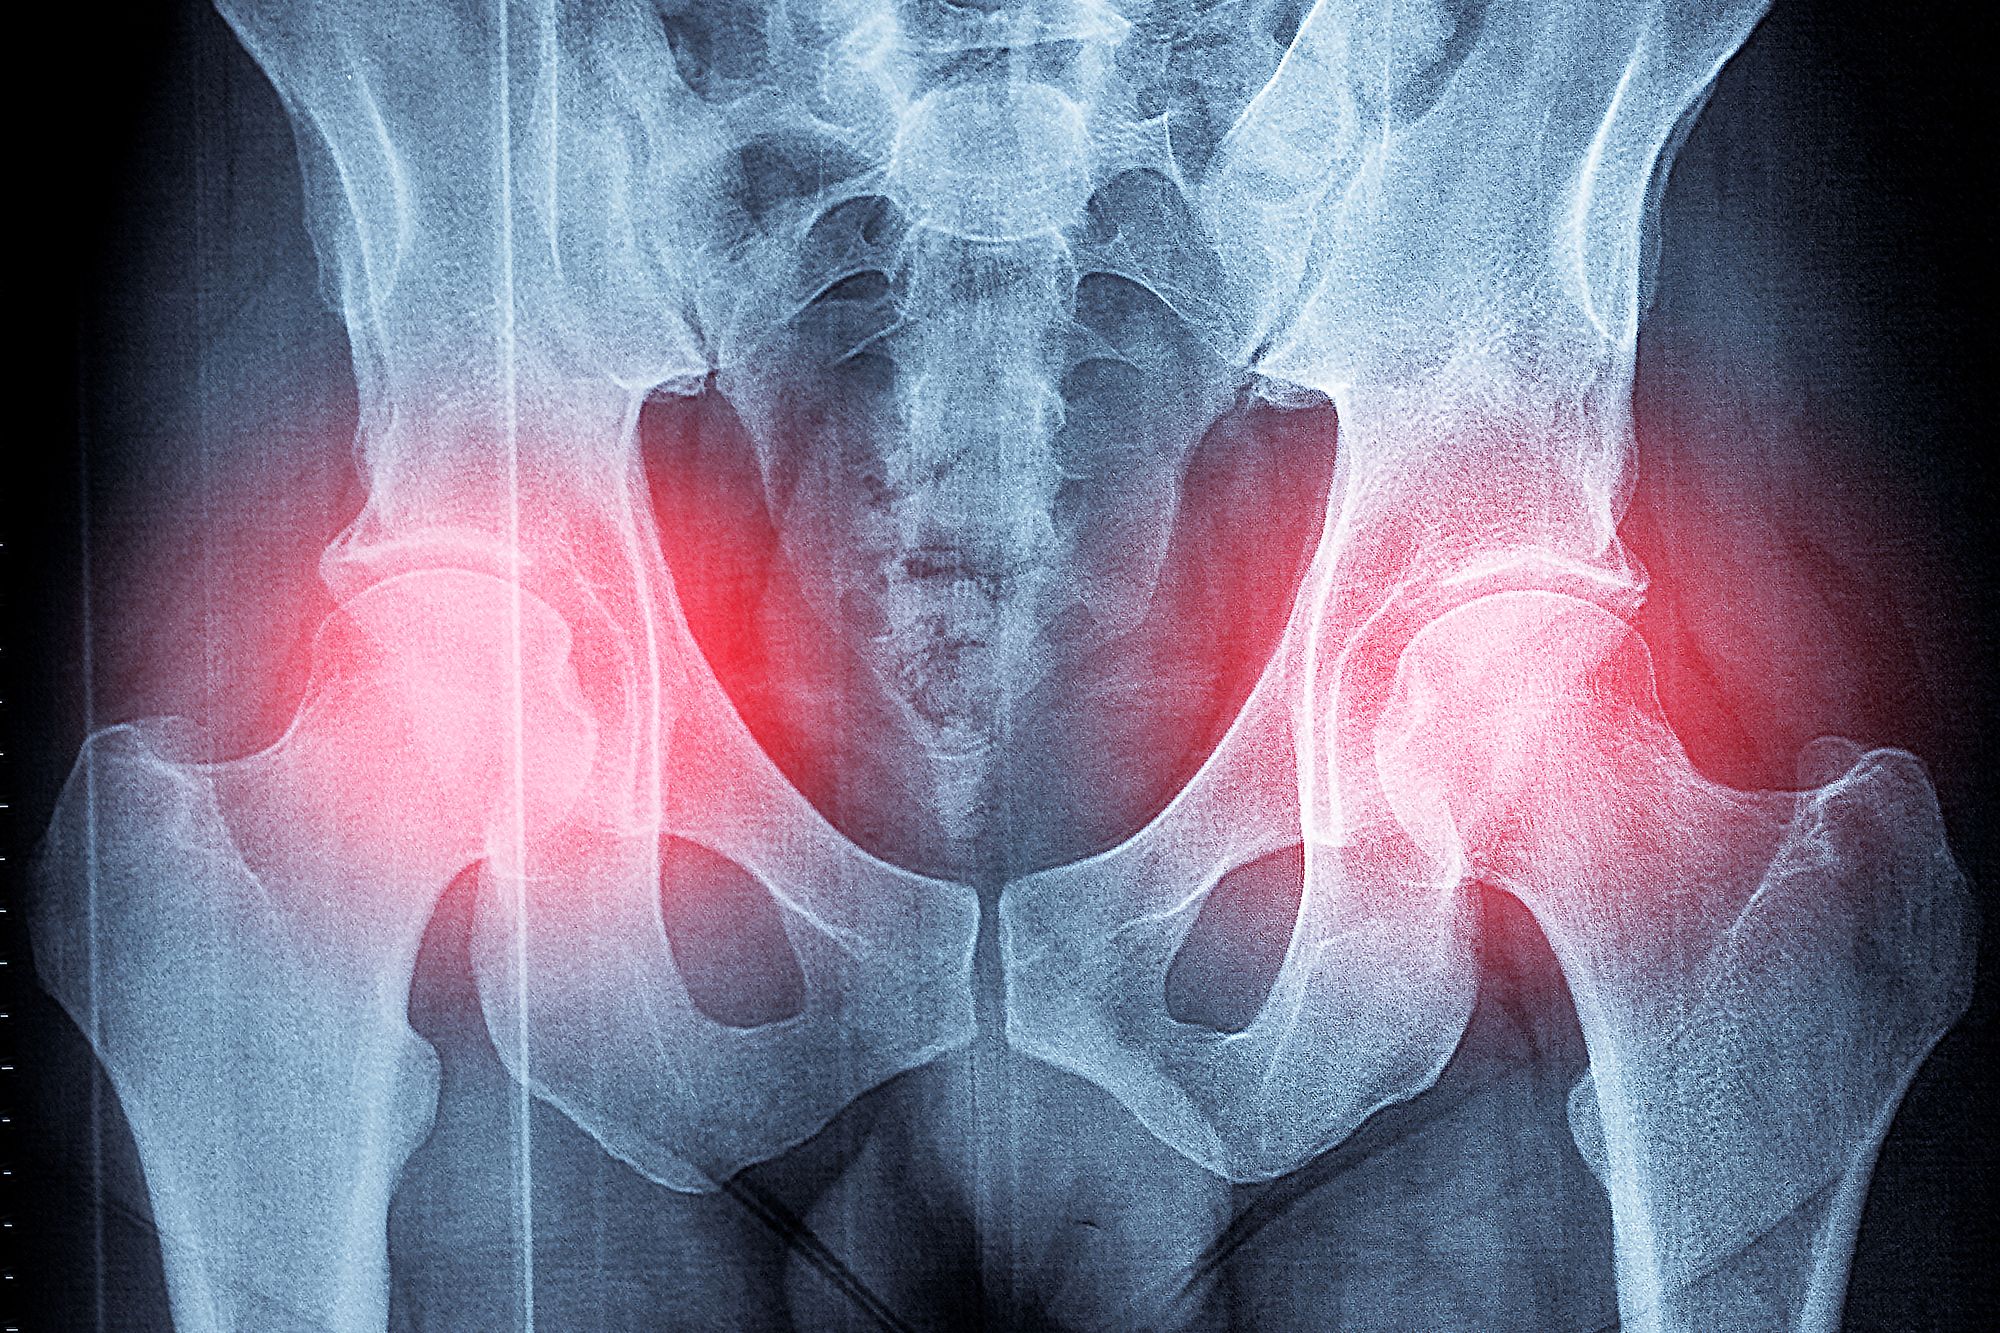

An image collage containing 1 images, Image 1 shows X-ray of a man's pelvis with a possible hip fracture

Patients are being denied hip and knee ops due to their weight, Arthritis UK saysCredit: Getty